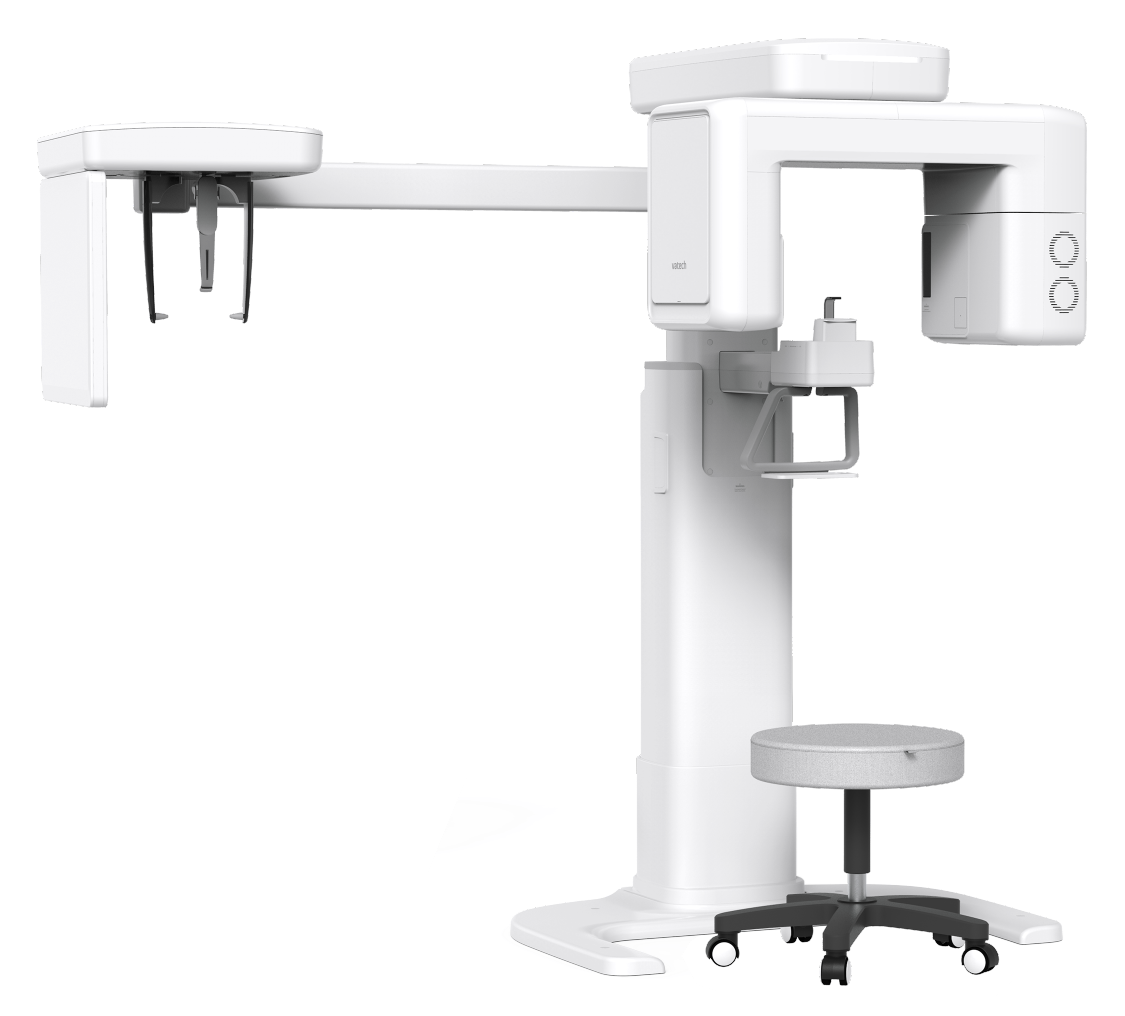

| FUNCTION | FOCAL SPOT SIZE | CT FOV SIZE | VOXEL SIZE | SCAN TIME | GRAY SCALE | TUBE VOLTAGE / CURRENT | WEIGHT |

|---|---|---|---|---|---|---|---|

| CT + Pano + Ceph | 0.5 mm (IEC 60336) | 8x8 cm | 0.2 mm / 0.3 mm |

CT 18 sec PANO 11.9 sec / 14.1 sec |

14 Bit | 60 ~ 99 kV / 4 ~ 10 mA |

Without CEPH unit 238.76 lbs. (Without Base) 353.84 lbs. (With Base) With CEPH unit 296.08 lbs. (Without Base) 411.16 lbs. (With Base) |

* The specifications are subject to change without prior notice.